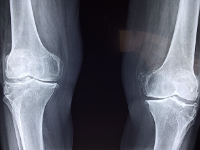

무릎 관절에 좋은 음식 무릎 관절 관리 방법 등 정보에 대해 알아보도록 하겠습니다. 무릎 관절은 우리 몸에서 가장 중요한 관절 중 하나로, 걷기, 뛰기, 앉기 등 다양한 움직임에 참여합니다. 하지만 무릎 관절은 나이가 들면서 퇴행성 변화가 일어나기 쉽고, 과도한 운동이나 부상으로 인해 손상될 수도 있습니다.

무릎 관절염 증상

무릎 관절염은 다음과 같은 4가지 증상을 보입니다.

1. 관절통 : 무릎 관절염의 가장 대표적인 증상으로, 보행이나 운동 시에 통증이 생기거나, 앉았다 일어날 때 통증이 심해지는 경우가 많습니다. 초기에는 휴식을 취하면 통증이 완화되지만, 진행되면 잠을 설치거나 일상생활에 지장을 주는 정도로 통증이 심해집니다.

2. 부종 : 무릎 관절에 염증이 생기면 관절 주변에 부종이 발생합니다. 부종은 관절의 움직임을 제한하고 통증을 악화시킵니다. 부종은 날씨가 춥거나 습한 경우에 더 심해지기도 합니다.

3. 뻣뻣함 : 무릎 관절염이 진행되면 연골이 없어지고 관절면이 불규칙해지면서 관절의 움직임이 뻣뻣해집니다. 특히 오랜 시간 앉아 있거나 잠자고 일어날 때 더욱 느껴집니다. 관절의 움직임이 제한되면 근력도 감소하고 변형도 발생할 수 있습니다.

4. 마찰음 : 무릎 관절염에서는 연골이 마모되고 골극이 형성되면서 관절 운동 시에 마찰음이 들리거나 느껴집니다. 마찰음은 삐걱거리는 소리나 탁탁하는 소리로 나타날 수 있으며, 이는 연골의 손상 정도를 나타내는 지표가 될 수 있습니다.